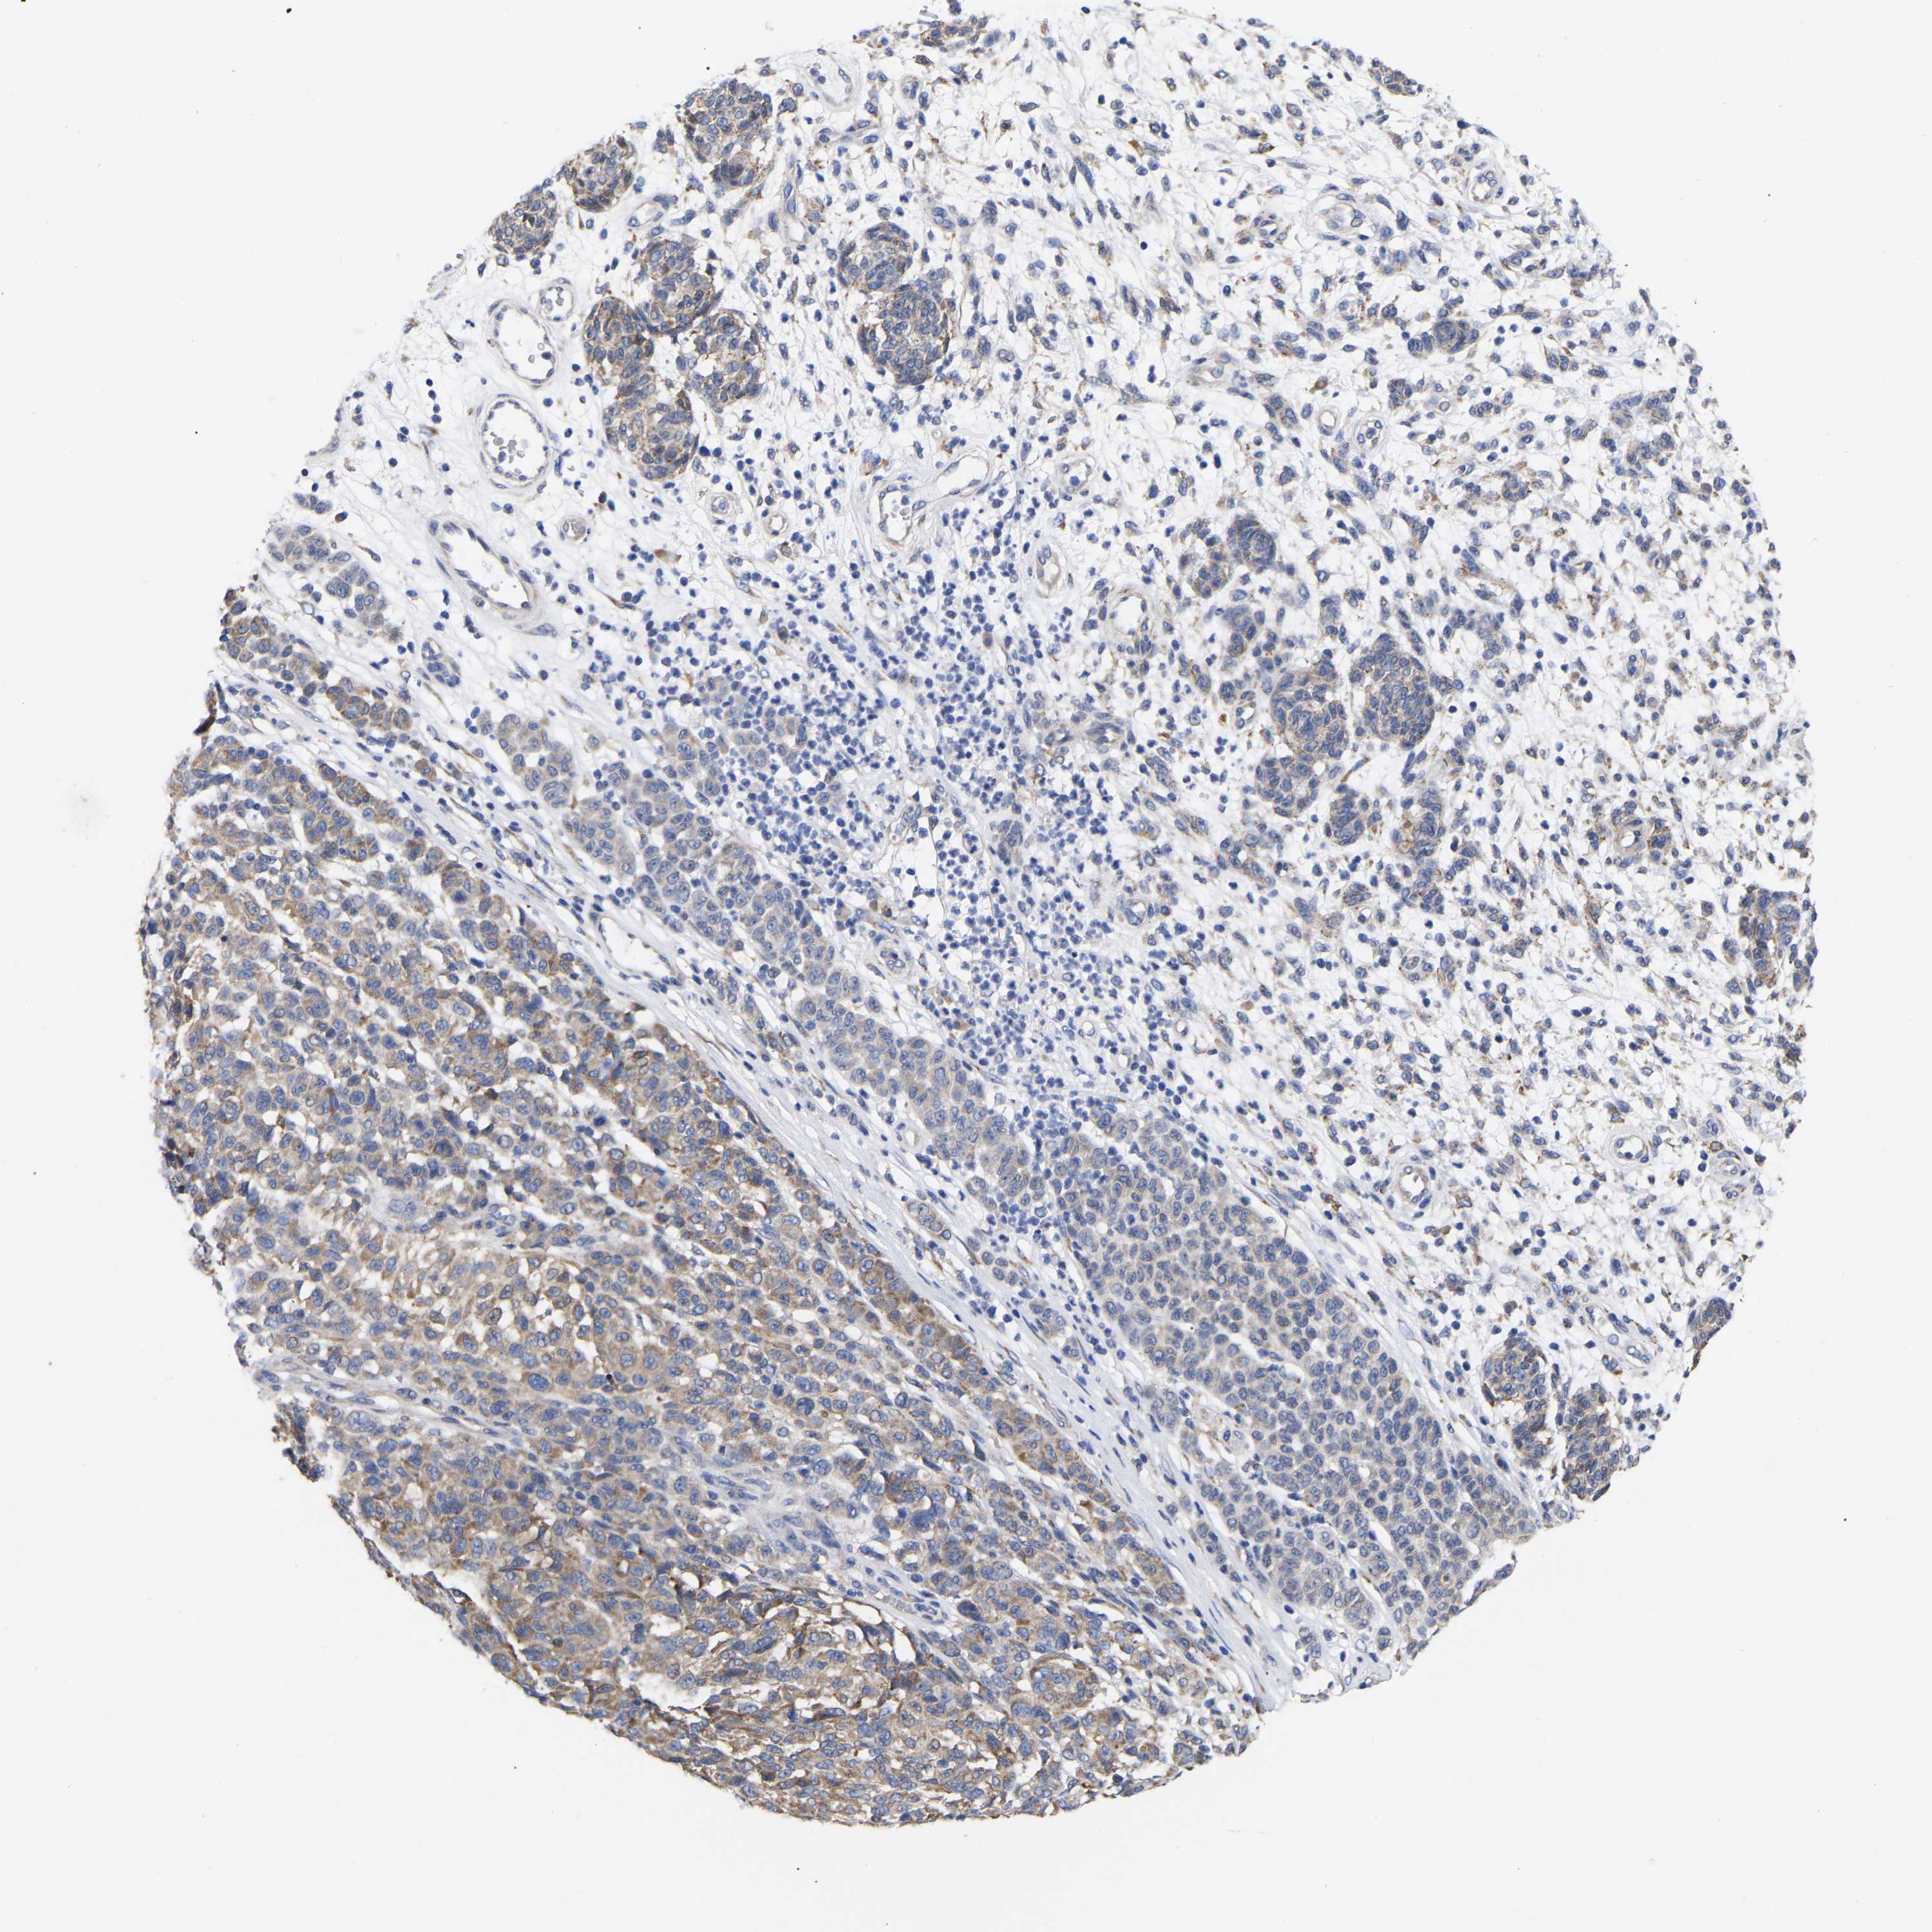

MELANOMA - Protein expressioni

A mouse-over function shows sample information and annotation data. Click on an image to view it in a full screen mode. Samples can be filtered based on level of antibody staining by selecting one or several of the following categories: high, medium, low and not detected. The assay and annotation is described here.

Note that samples used for immunohistochemistry by the Human Protein Atlas do not correspond to samples in the TCGA dataset.

Antibody stainingi

Antibody staining in the annotated cell types in the current human tissue is reported as not detected, low, medium, or high, based on conventional immunohistochemistry profiling in selected tissues. This score is based on the combination of the staining intensity and fraction of stained cells.

Each image is clickable and will lead to virtual microscopy that enables deeper exploration of all samples and also displays staining intensity scores, fraction scores and subcellular localization as well as patient and tissue information for each sample.

Antibody HPA018453

Antibody HPA019055

Antibody HPA028849

Antibody CAB034170

Malignant melanoma, NOS

Malignant melanoma, Metastatic site